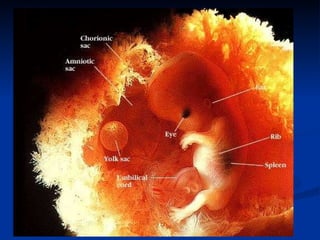

The document discusses embryonic development in humans. It begins with fertilization and cleavage, followed by gastrulation where the three germ layers are formed. During this time the primitive streak and Henson's node develop. Organogenesis then occurs, forming individual organs from the germ layers. Mammalian development includes the allantois and notochord. In humans, the placenta forms and gestation occurs over three trimesters, with major organ structures present by the first trimester.